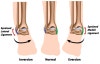

발목 염좌의 분류(Classification)

1. Lateral ankle sprain(85%)

1) The AFTL is injured in 65% and combined injuries of the AFTL and CFL occur in 20%

2) Plantar flexion and inversion

2. Syndemotic sprain(10%)

1) High ankle sprain, Anterior tibiofibular sprain

2) Dorsiflexion and/or eversion

3. Medial ankle sprain(5%)

1) 임상적으로 결코 파열되지 않습니다(MM avulsion fx가 rupture전에 발생합니다).

2) Talus moves laterally causing a break in the fibular superior to the inferior tibio-fibular joint(Pott fracture dislocation).

3) Eversion

발목 염좌의 단계(Grade)

Grade 1 : 염좌 상태로 불안정성을 나타내지 않는 상태의 불완전 파열

Grade 2 : 약간의 불안정성을 나타내는 정도의 부분적 파열

Grade 3 : 불안정성이 확실하고 심각한 완전 파열ㅂ